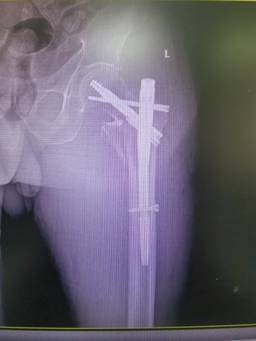

無獨有偶,石化醫(yī)院骨科隨后又收治了一位78歲左股骨轉(zhuǎn)子間骨折患者,團(tuán)隊再次自主完成高齡股骨轉(zhuǎn)子間骨折PFBN固定術(shù),術(shù)后患者恢復(fù)良好。

面對“人生最后一次骨折”,現(xiàn)在患者有了更好的選擇。據(jù)了解,目前PFBN技術(shù)在國內(nèi)開展屈指可數(shù)。此次石化醫(yī)院骨科2例手術(shù)的成功,填補(bǔ)了本地區(qū)該項技術(shù)的空白,也標(biāo)志著科室在老年髖部骨折微創(chuàng)手術(shù)領(lǐng)域又邁入了一個新的臺階。